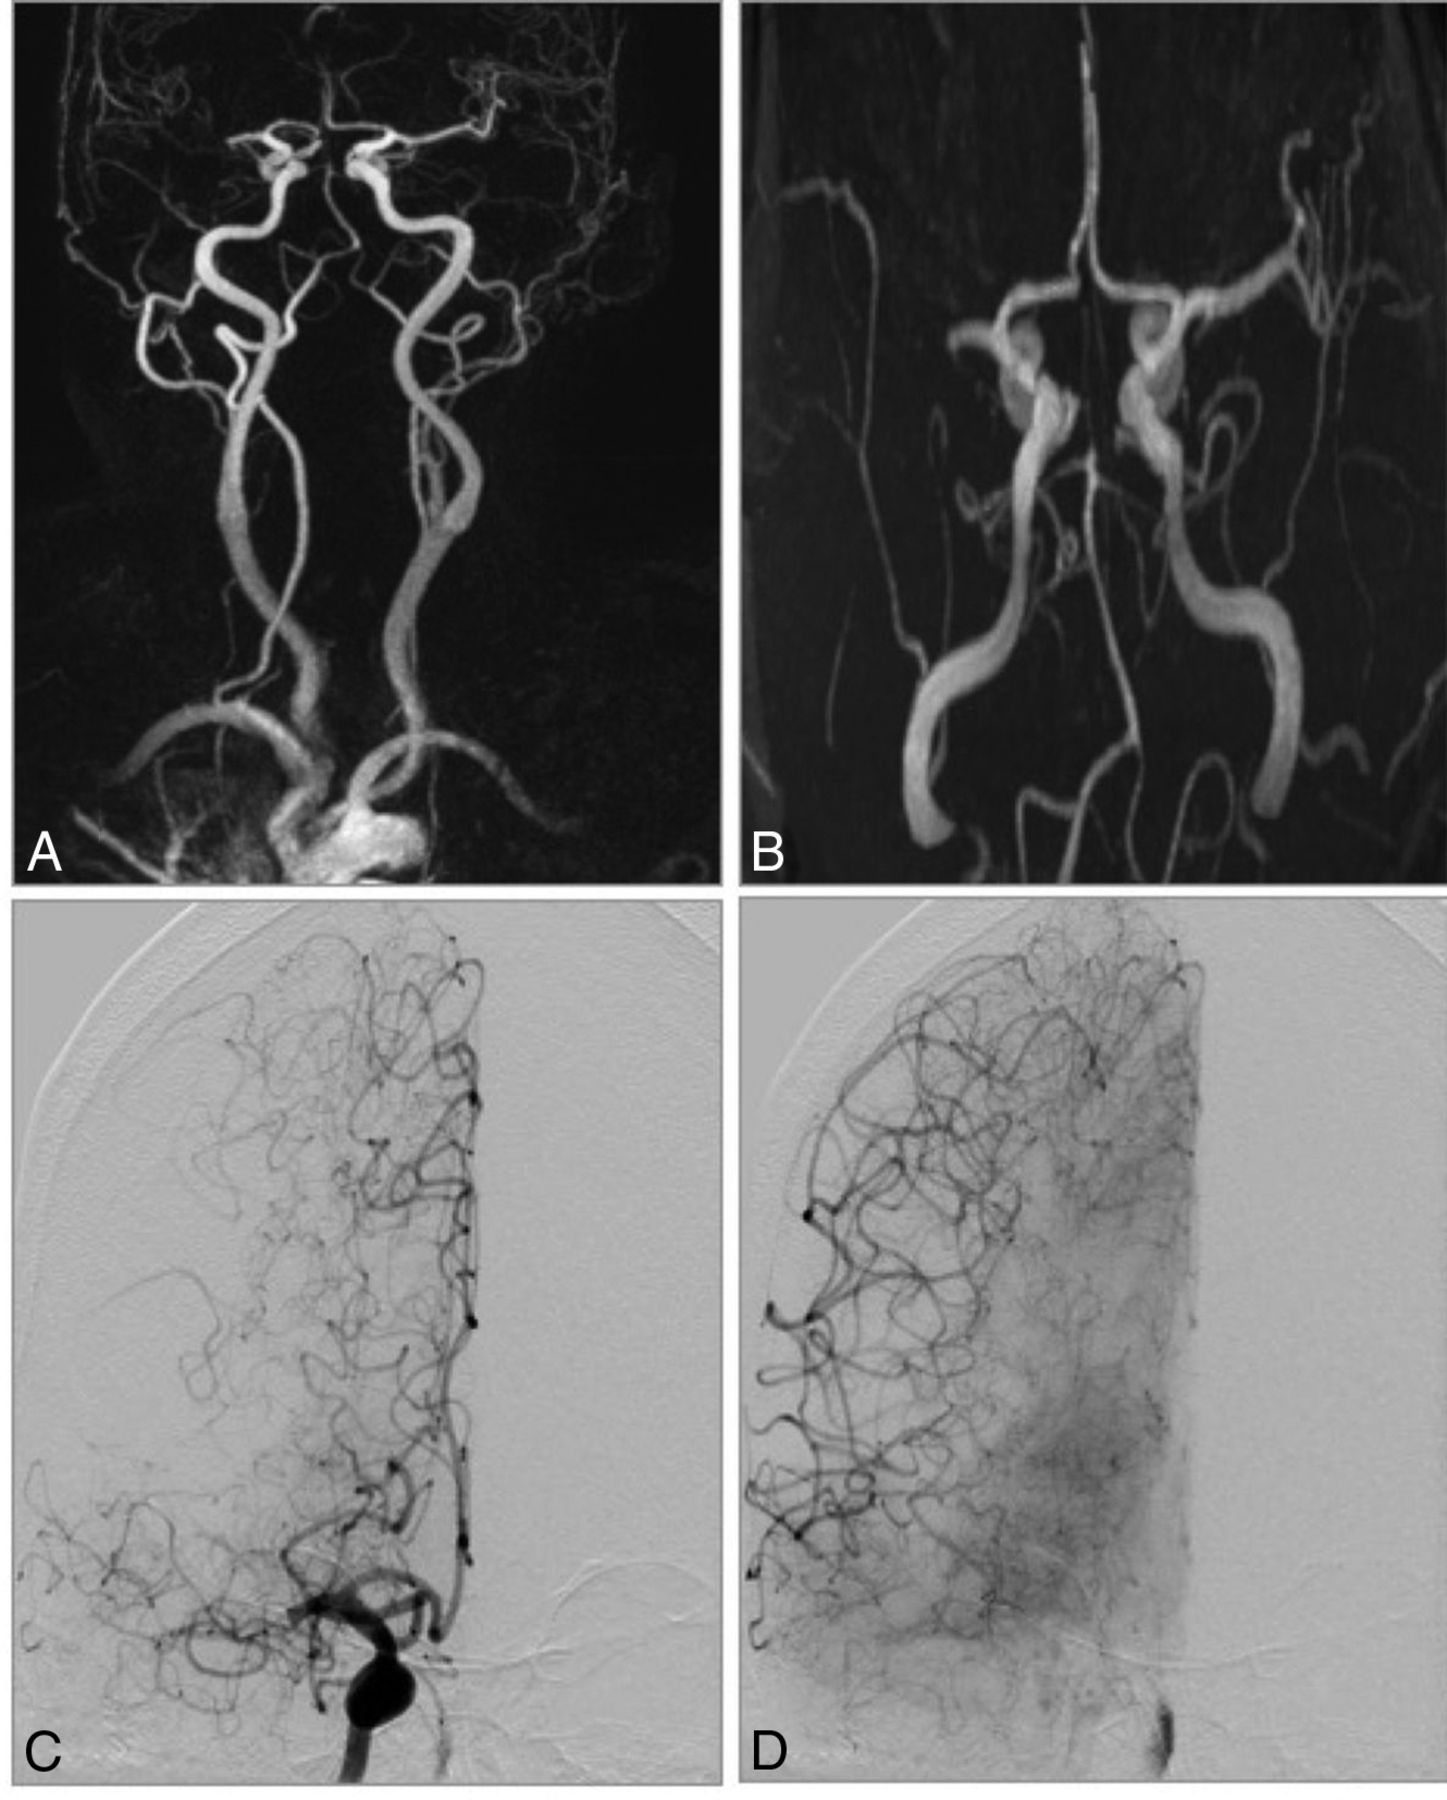

CE-MRA and TOF-MRA in an 81-year-old man with acute stroke symptoms before treatment. A, CE-MRA shows a tandem occlusion of the proximal ICA and right M1 segment with poor collaterals. B, TOF-MRA shows an occlusion of distal ICA (carotid-L). C and D, DSA confirms the tandem occlusion and CE-MRA diagnosis.

We analyzed the collateral status in the reference standard DSA with a very good interrater agreement with κ = 0.92 (95% CI, 0.80–0.99). Interrater agreement for assessing the collaterals was considered good for CE-MRA with κ = 0.70 (95% CI, 0.56–0.85) and moderate for TOF-MRA with κ = 0.40 (95% CI, 0.19–0.62). Imaging examples are given in Fig 3.

The collateral score was identical between DSA and CE-MRA in 87.7% of cases (57/65) with no statistically significant difference (P = .125), while there was a significant difference in collateral assessment between TOF-MRA and DSA (P < .001) and only 21.5% (14/65) of cases were assigned correctly. Imaging examples are shown in Fig 4.

CE-MRA and TOF-MRA in a 72-year-old woman with acute stroke symptoms before treatment. A, CE-MRA shows an occlusion of right M1 segment with good collaterals. B, TOF-MRA shows an occlusion of the M1 segment and poor collaterals. C and D, DSA shows a right-sided M1 occlusion with good collaterals as in the CE-MRA.